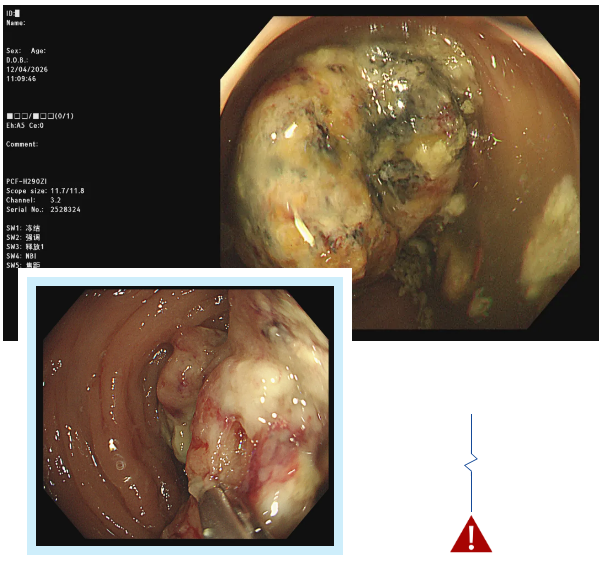

经无痛肠镜检查,吕主任发现李阿姨脾区肠壁增厚,肠道已经出现狭窄,肠镜无法顺利通过。随后取肿物进行活检,最终确诊为结肠癌。这个结果给李阿姨和她的家人敲响了警钟,也让我们深刻意识到,肠道发出的一些看似不起眼的信号,可能隐藏着致命的危机。

肠镜插入与观察:待患者进入睡眠状态后,医生会将带有摄像头的肠镜从肛门缓缓插入肠道,通过肠道蠕动逐步推进。在插入过程中,医生会不断注入少量空气,使肠道扩张,以便清晰地观察肠道黏膜的情况。肠镜上的摄像头会将肠道内部的画面实时传输到显示器上,医生可以仔细查看肠道内是否有息肉、炎症、溃疡、肿瘤等病变。如果发现可疑病变,医生还可以通过肠镜上的活检通道取少量组织进行病理检查,以明确病变的性质。